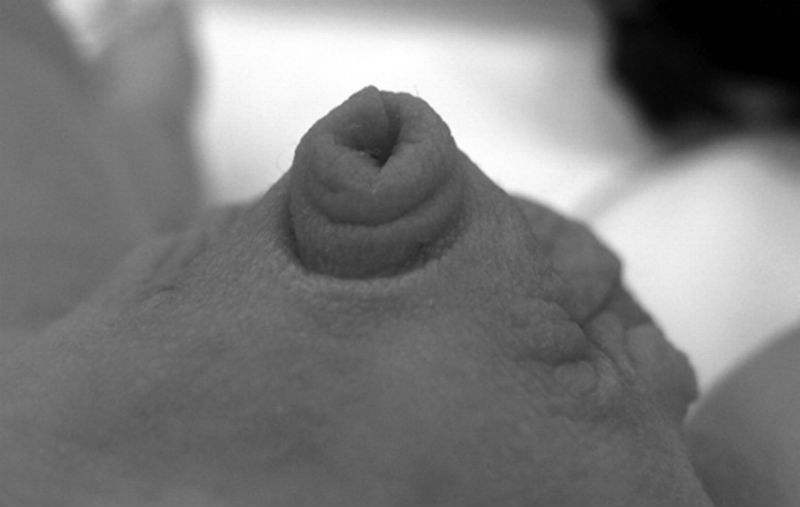

BS Hùng cho hay, vùi dương vật là một dị dạng bẩm sinh của bộ phận sinh dục. Trong đó thân dương vật và quy đầu bị vùi trong lớp da quy đầu liên tục với bìu hoặc thành bụng, nên không nhô lên khỏi lớp da trước xương mu.

Nếu nhìn bên ngoài không thấy thân dương vật. Khi dùng ngón tay ấn vào gốc dương vật để kéo da dương vật và bao quy đầu về phía xương mu sẽ thấy được thân dương vật. Khi buông tay ra thì thân dương vật bị biến mất trong ngấn da.

Vùi dương vật bẩm sinh gây khó khăn cho việc tiểu tiện của các bé trai. Nếu tình trạng kéo dài có thể gây biến chứng xơ, tắc quy đầu, nhiễm trùng tiểu.